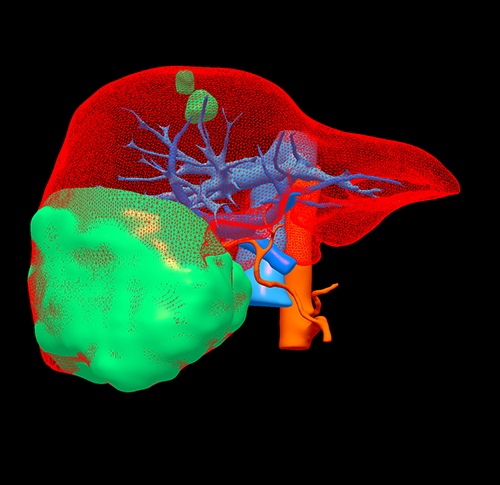

右肝巨大肝血管瘤---S56巨大肝血管瘤切除